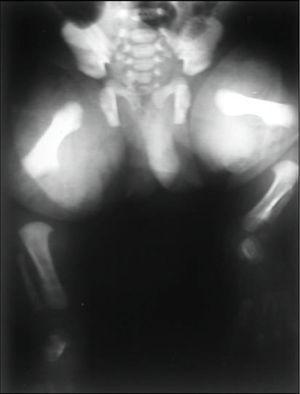

Los hallazgos radiológicos confirmaron el diagnóstico de DML: acortamiento de los huesos largos de extremidades, más marcado en antebrazos y piernas con marcada angulación de la diáfisis radial, cúbito ancho y corto, deformidad de la cabeza humeral (fig. 1); cuello femoral corto con grandes trocánteres y cóndilos, acortamiento, ensanchamiento y angulación lateral de la tibia con hipoplasia de peroné a expensas de su porción proximal (fig. 2) e hipoplasia mandibular. El cariotipo fue normal, 46 XY. No se encontraron malformaciones asociadas.

Figura 1. Angulación de la diáfisis radial, cúbito ancho y corto e hipoplasia de la porción proximal del húmero.